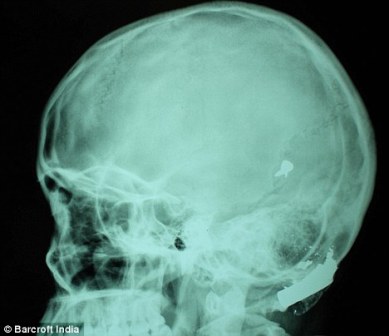

其中一顆子彈擊中她的左中耳,穿透了她的耳骨,然后擊中頭骨,嵌在了腦子里。另外兩顆子彈分別擊中她的右臂和心臟。印度Lok Nayak醫(yī)院的醫(yī)生稱,赫娜能夠康復(fù)完全是奇跡,她也足夠幸運(yùn)。她的主治醫(yī)生稱:“當(dāng)我們看到她的情況時(shí),被嚇了一跳,幸運(yùn)的是她活了下來(lái)!

這顆子彈沒(méi)有損壞大腦中控制身體機(jī)能的部分。盡管赫娜的手術(shù)很成功,但醫(yī)生表示,她還有出現(xiàn)感染和并發(fā)癥的可能。子彈毀掉了她的中耳,可能導(dǎo)致她耳聾。(楊柳)